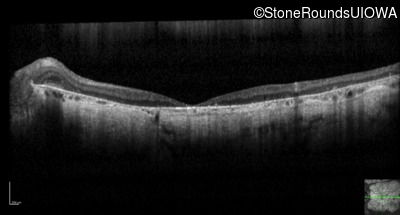

Optical Coherence Tomography - Right - 20/200 +1 sc

Exemplar / OCT Stack

Optical Coherence Tomography - Right - 10/125 sc